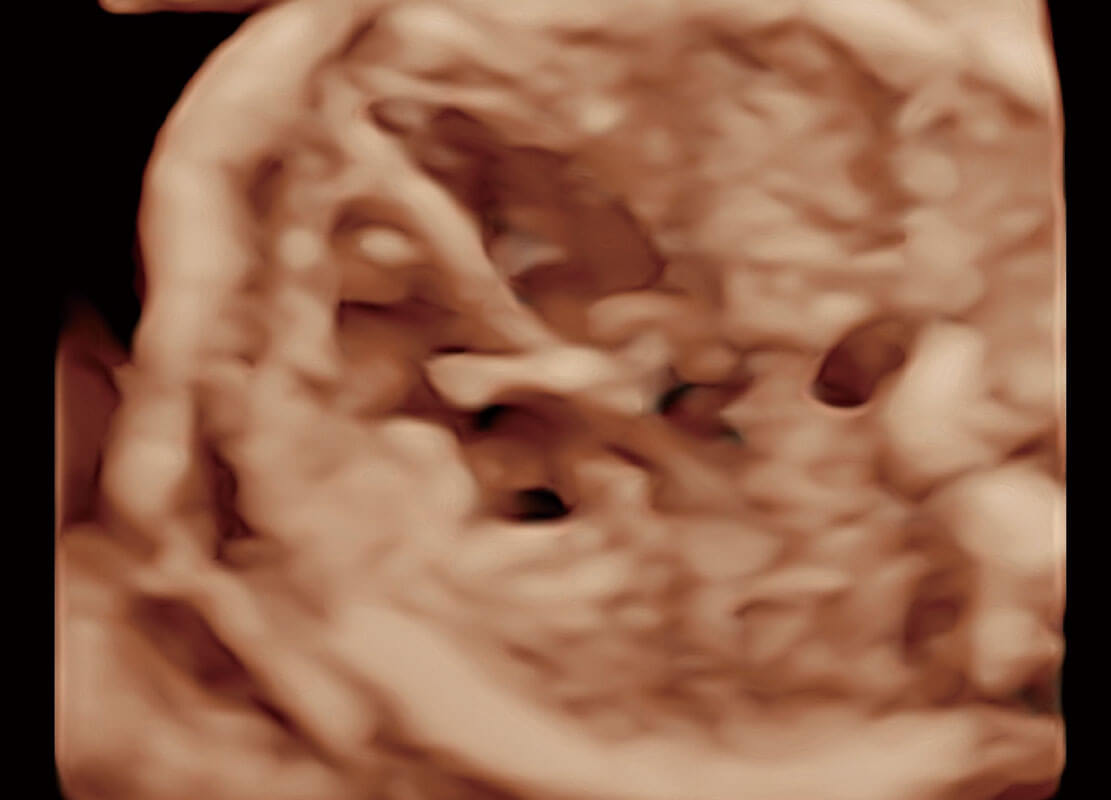

P60搭载一系列胎儿心脏成像技术,实现精细的胎儿心脏评估。

胎心容积成像